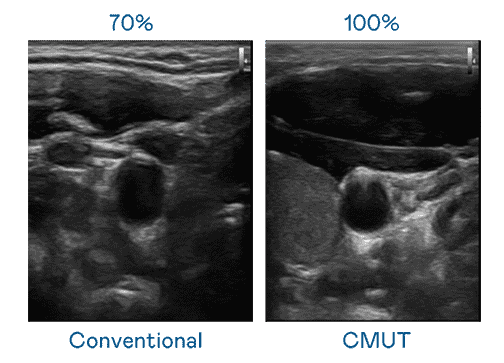

CMUT 技术是一种用电容式微机电元件来产生超音波讯号的技术。。。。与传统 PZT 压电式技术相比,,,CMUT 频宽增加 30%,,,,更宽频的超音波讯号让影像解析度大幅提升,,,,是实现高影像品质医疗超音波扫描、、促进精准医疗发展的关键技术。。。。

大频宽带来超清晰影像

超音波影像的解析度高低,,首先取决于探头能发出的讯号频宽。。。尊时凯龙 CMUT 可提供高清晰的超音波讯号,,提供高频宽、、、、高灵敏度、、、、影像纹理细节更高的超音波影像,,协助医护人员缩短影像判读时间及利用精准的医疗影像进行诊断。。。。